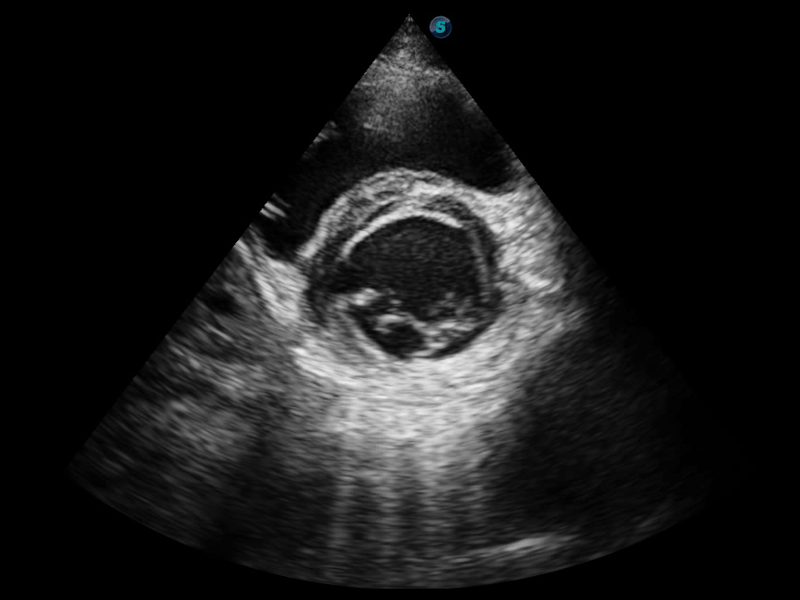

凭借狗万官方网站先进的成像技术和优异的探头技术提供的清晰的图像表现,您可以更自信地做出临床决策。

相控阵探头